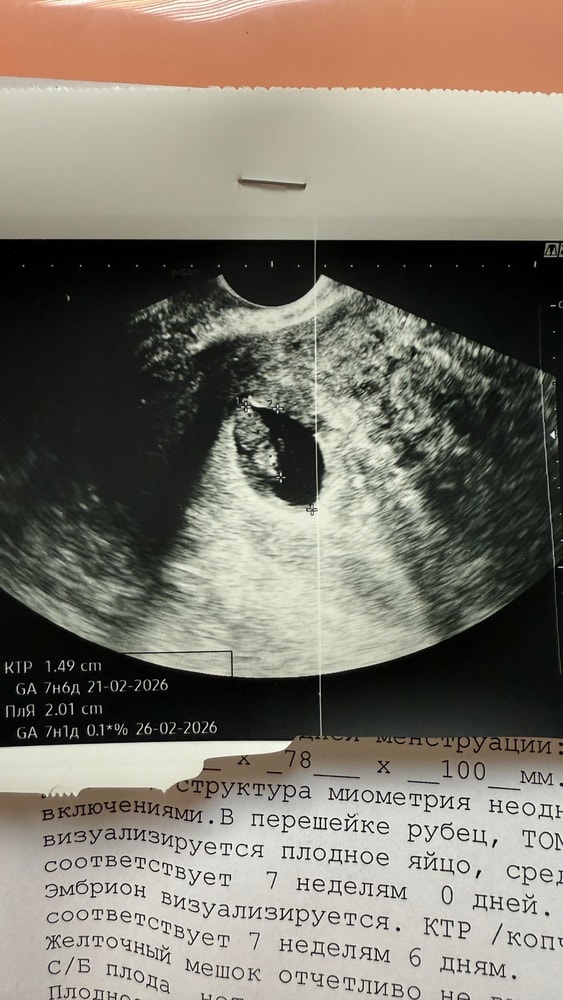

Замер мой креветкин, организм не вытянул даже с утриком пя